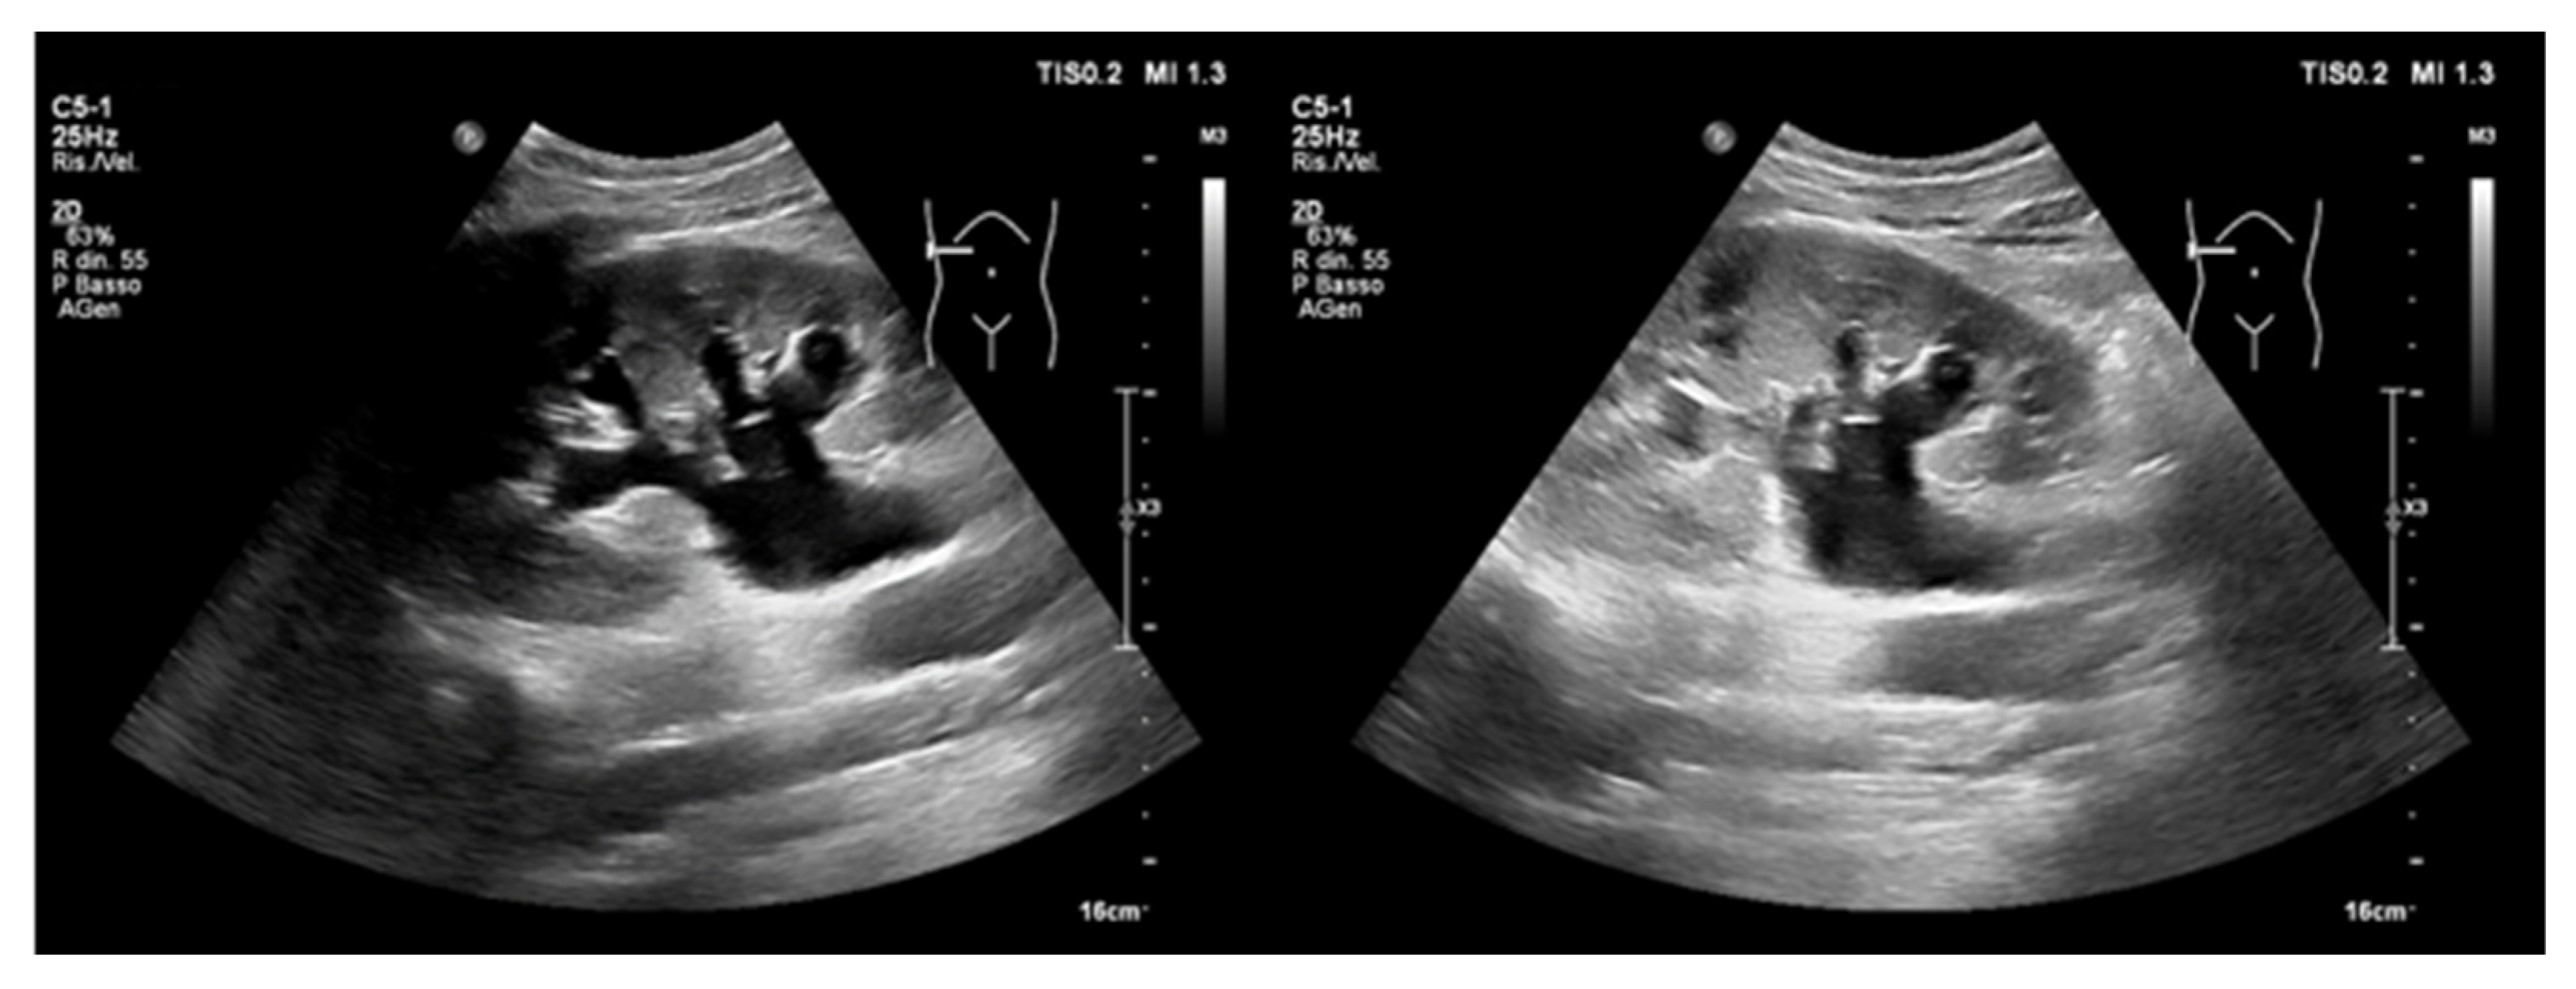

4. Point-of-Care Abdominal Ultrasound

4.1. Acute Abdominal Pain

- (A)

- Intraperitoneal free fluid

- Abdominal aortic aneurysm

4.2. Acute Kidney Injury

4.2.2. Obstructive AKI